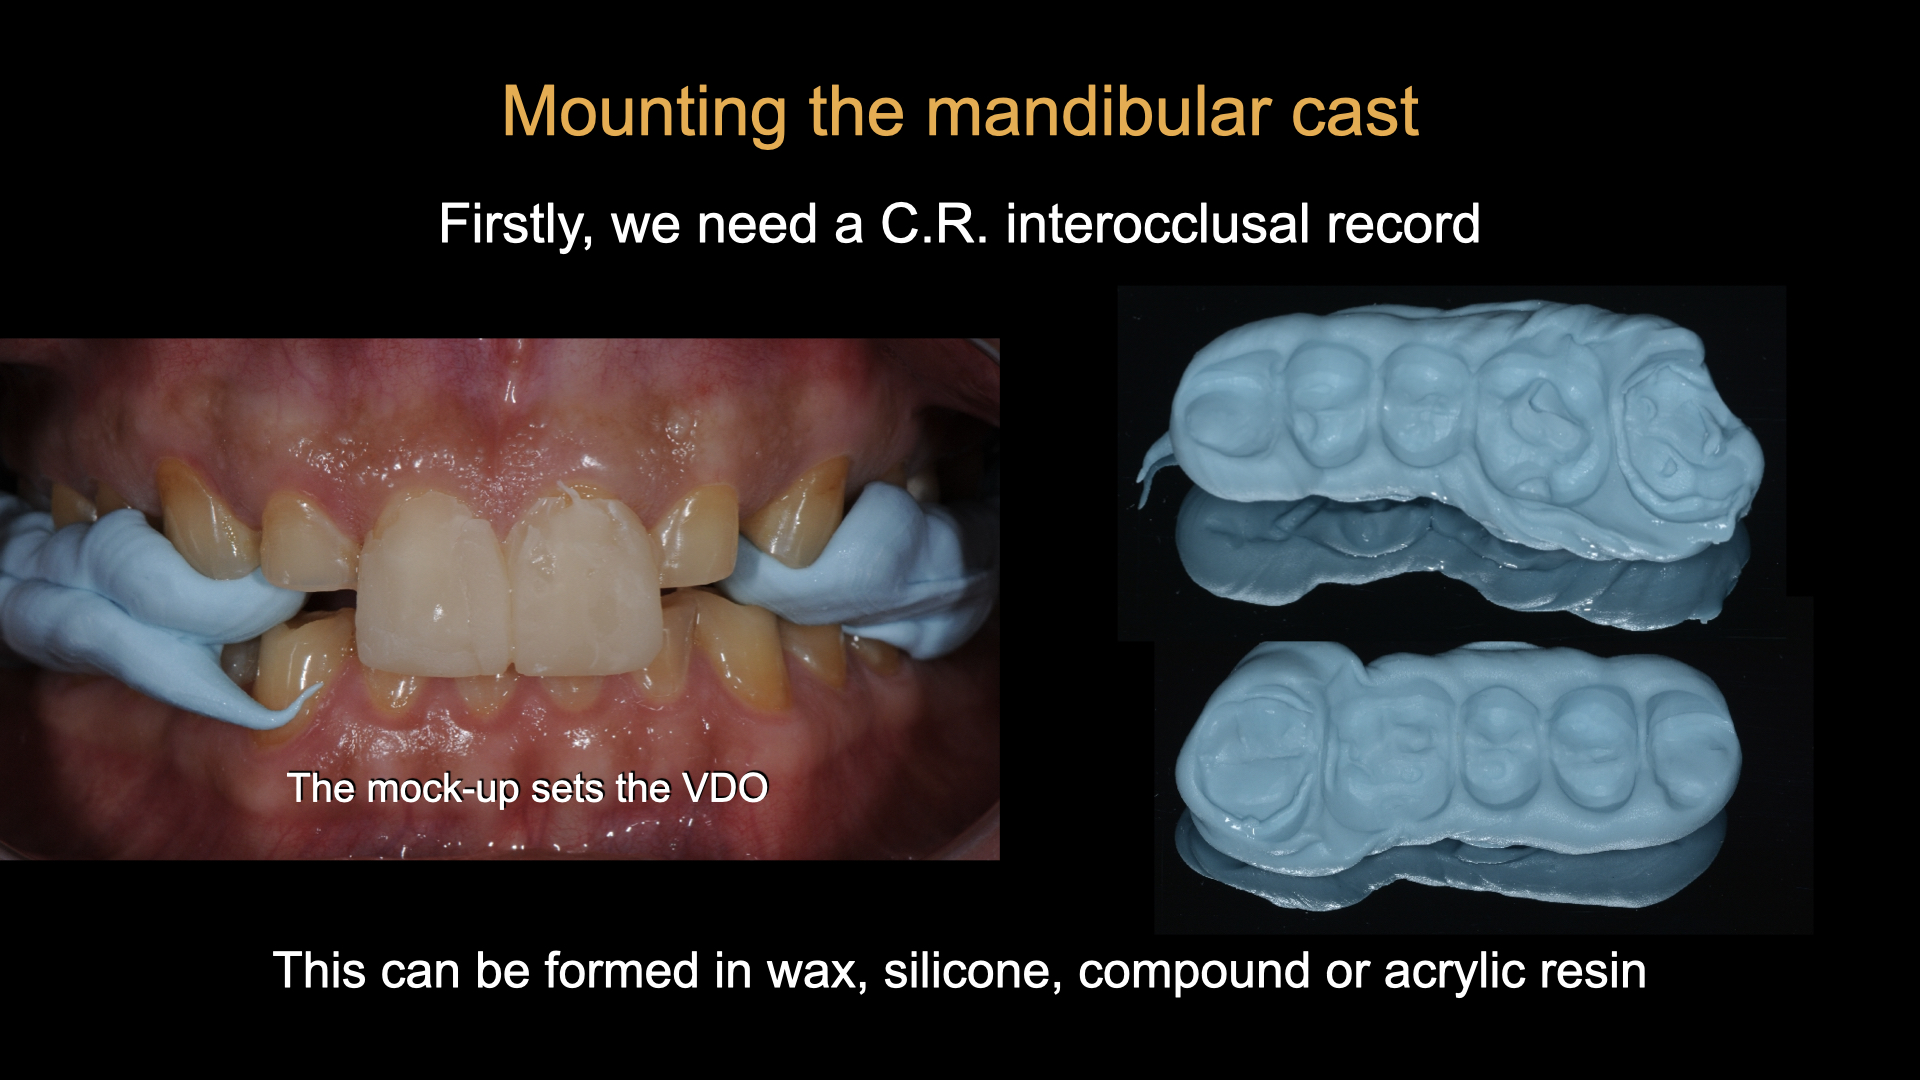

A Day of Occlusion - Updated Program !

This full, 1-Day (7 hour) lecture and demonstration program was presented by Dr Michael Mandikos in November 2025. It has …

Understanding Occlusion and Splints

This is a recording of the full, 1-Day lecture and demonstration program as presented by Dr Michael Mandikos. The course …